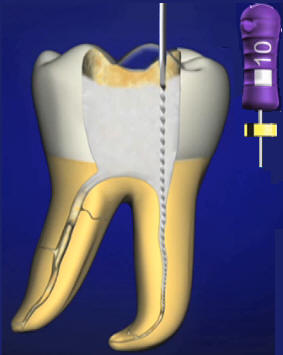

Se debe rectificar la cámara para que la lima acceda en forma vertical "A" para ello se utiliza la fresa SX  ó Pre RaCe

Acceso vertical con lima 10 manual